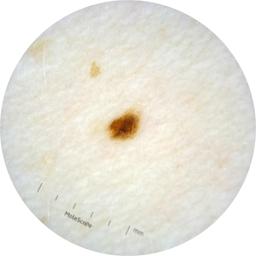

ISIC_2261268

2061 x 2061

Clinical

Field Value

acquisition_day 307

age_approx 50

anatom_site_1 Trunk

anatom_site_2 Posterior trunk

anatom_site_general posterior torso

concomitant_biopsy False

diagnosis_1 Benign

diagnosis_confirm_type single image expert consensus

family_hx_mm False

fitzpatrick_skin_type I

image_manipulation instrument only

image_type dermoscopic

lesion_id IL_8976478

patient_id IP_9156603

personal_hx_mm True

sex female